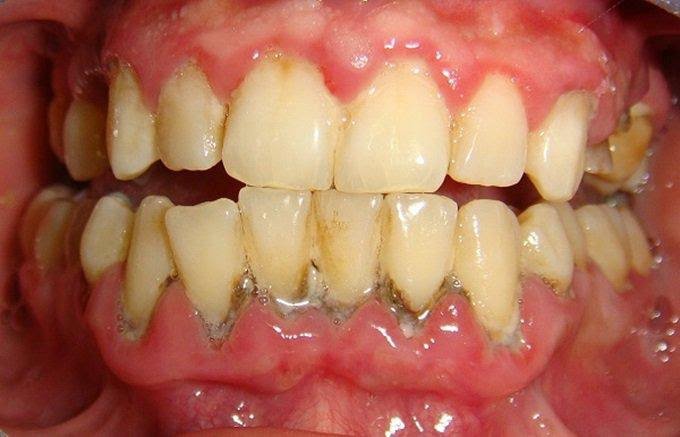

Hình ảnh cao răng bám đầy răng bệnh nhân

- Hạn chế nguy cơ mắc các bệnh lý răng miệng: cao răng là nơi trú ngụ của rất nhiều vi khuẩn có hại – chúng chính là nguyên nhân hàng đầu gây ra các bệnh lý như sâu răng, tụt lợi, viêm nha chu, mòn men răng,…

- Bảo vệ răng và xương hàm khỏe mạnh: vi khuẩn tích tụ trong cao răng theo thời gian sẽ xâm nhập vào sâu bên trong gây hư hỏng nướu và các tổ chức răng từ đó dẫn đến tiêu xương hàm và khiến răng bị lung lay, nguy hiểm hơn sẽ gây ra tình trạng mất răng hàng loạt.

Một số trường hợp khác thì thấy chân răng chảy máu trong lúc lấy cao răng. Tuy nhiên, bạn không cần phải lo lắng vì đây chỉ là một biểu hiện bình thường do lớp căng quá dày và bám sâu vào chân răng nên khi lấy cao răng sẽ tác động nhẹ tới phần nướu.